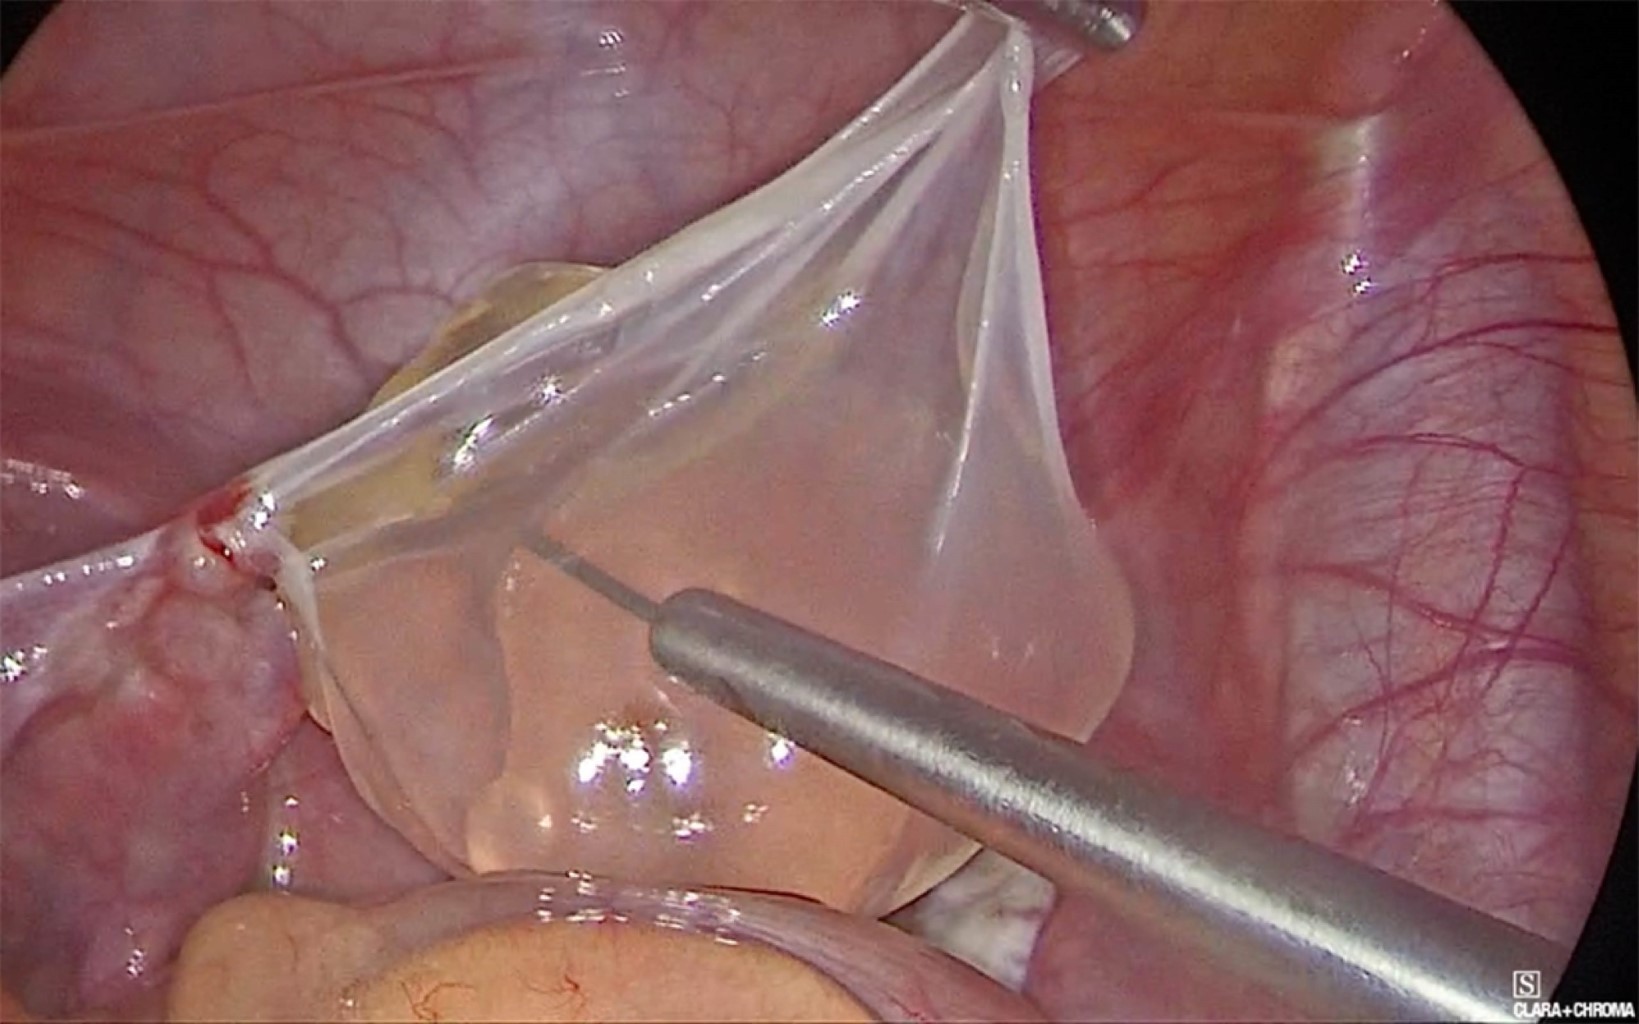

Se colocó trocar umbilical de 10 mm con lente de 30 grados, dos más de 5 mm en ambas fosas iliacas, encontrando en pelvis cuatro quistes de diferentes tamaños, siendo el mayor de 12 cm aproximadamente, otros de 7, 5 y 4 cm, con paredes delgadas y lisas, traslucidos, con contenido líquido seroso, dos sueltos en pelvis (Figuras 3 y 4) y dos adheridos ligeramente a ovario y trompa izquierda, retirados con bisturí armónico (Figura 5). Se puncionó con aguja, extrayendo de cada uno líquido seroso para estudio histopatológico y citoquímico. Se extrajeron las cápsulas en su totalidad; ovarios y útero, así como el resto de la cavidad sin alteraciones, se tomó biopsia de peritoneo y epiplón mayor. Se lavó pelvis y revisó hemostasia. La paciente cursó con evolución favorable, egresando a las 24 horas del procedimiento.

A nivel macroscópico los quistes en el MPMB pueden ser uniloculares o multiloculares; flotan libremente en la cavidad abdominal o se adhieren a las estructuras peritoneales, varían de 1 mm hasta 20 cm, se agrupan y forman masas similares a uvas en la cavidad peritoneal, por lo general contienen líquido transparente o hemorrágico.2